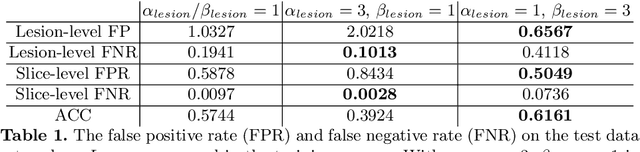

Prostate cancer (PCa) is one of the leading causes of death for men worldwide. Multi-parametric magnetic resonance (mpMR) imaging has emerged as a non-invasive diagnostic tool for detecting and localising prostate tumours by specialised radiologists. These radiological examinations, for example, for differentiating malignant lesions from benign prostatic hyperplasia in transition zones and for defining the boundaries of clinically significant cancer, remain challenging and highly skill-and-experience-dependent. We first investigate experimental results in developing object detection neural networks that are trained to predict the radiological assessment, using these high-variance labels. We further argue that such a computer-assisted diagnosis (CAD) system needs to have the ability to control the false-positive rate (FPR) or false-negative rate (FNR), in order to be usefully deployed in a clinical workflow, informing clinical decisions without further human intervention. This work proposes a novel PCa detection network that incorporates a lesion-level cost-sensitive loss and an additional slice-level loss based on a lesion-to-slice mapping function, to manage the lesion- and slice-level costs, respectively. Our experiments based on 290 clinical patients concludes that 1) The lesion-level FNR was effectively reduced from 0.19 to 0.10 and the lesion-level FPR was reduced from 1.03 to 0.66 by changing the lesion-level cost; 2) The slice-level FNR was reduced from 0.19 to 0.00 by taking into account the slice-level cost; (3) Both lesion-level and slice-level FNRs were reduced with lower FP/FPR by changing the lesion-level or slice-level costs, compared with post-training threshold adjustment using networks without the proposed cost-aware training.